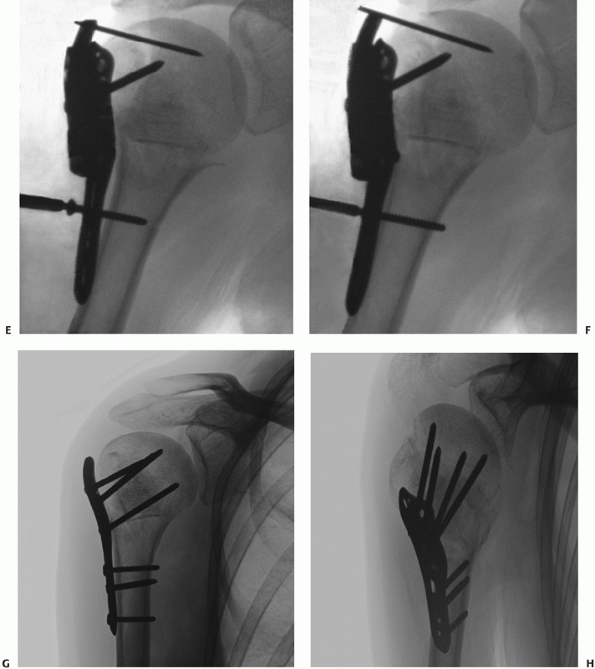

torsional redisplacement of the shaft from the head and to provide

additional fixation of reduced tuberosity fragments. This technique is

the most widely used method to treat displaced but salvageable two-,

three-, and four-part fractures. Several key steps are identified,

which are critical to the success of the reconstruction.

The procedure can be performed through a deltopectoral or extended

deltoid-splitting approach, identifying and protecting the anterior

branch of the axillary nerve before any fracture manipulation or